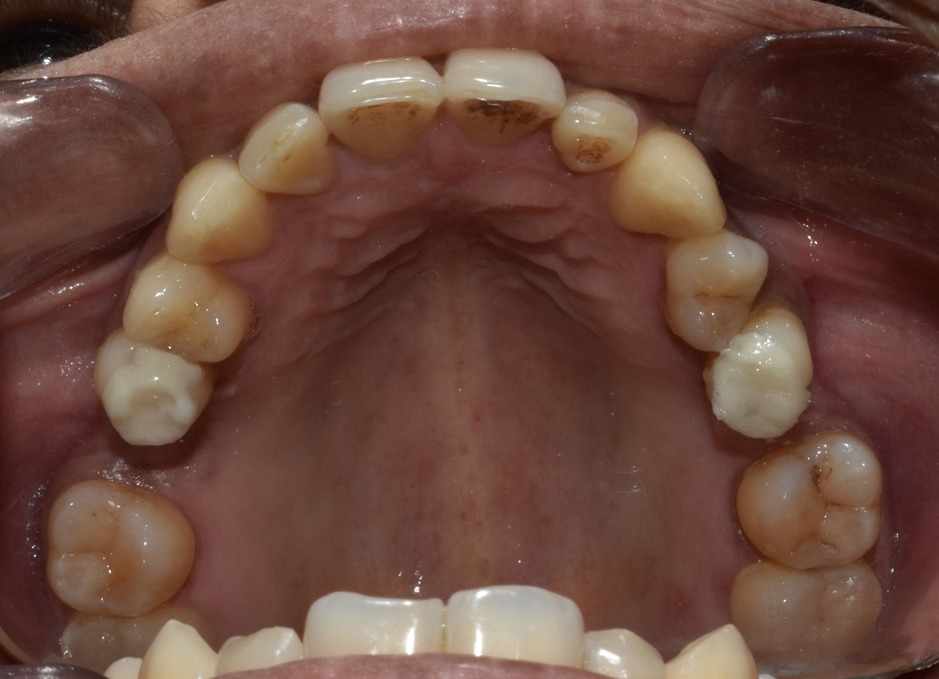

Before & After Results

At Aline Dent, we take pride in delivering visible and lasting improvements in our patients’ smiles. Our before-and-after results highlight the effectiveness of modern dental treatments combined with personalized care. This gallery showcases real dental cases treated at our clinic, giving you a clear idea of how different dental concerns can be corrected with the right treatment approach.

From minor corrections to complete smile enhancements, these teeth transformation results demonstrate how professional dental care can improve both oral health and appearance. Our experienced dental team carefully evaluates each patient’s needs and creates customized treatment plans to achieve natural, healthy, and confident smiles.

In this gallery, you will find a variety of smile makeover cases, including treatments for crooked teeth, gaps, discoloration, damaged teeth, and other common dental concerns.